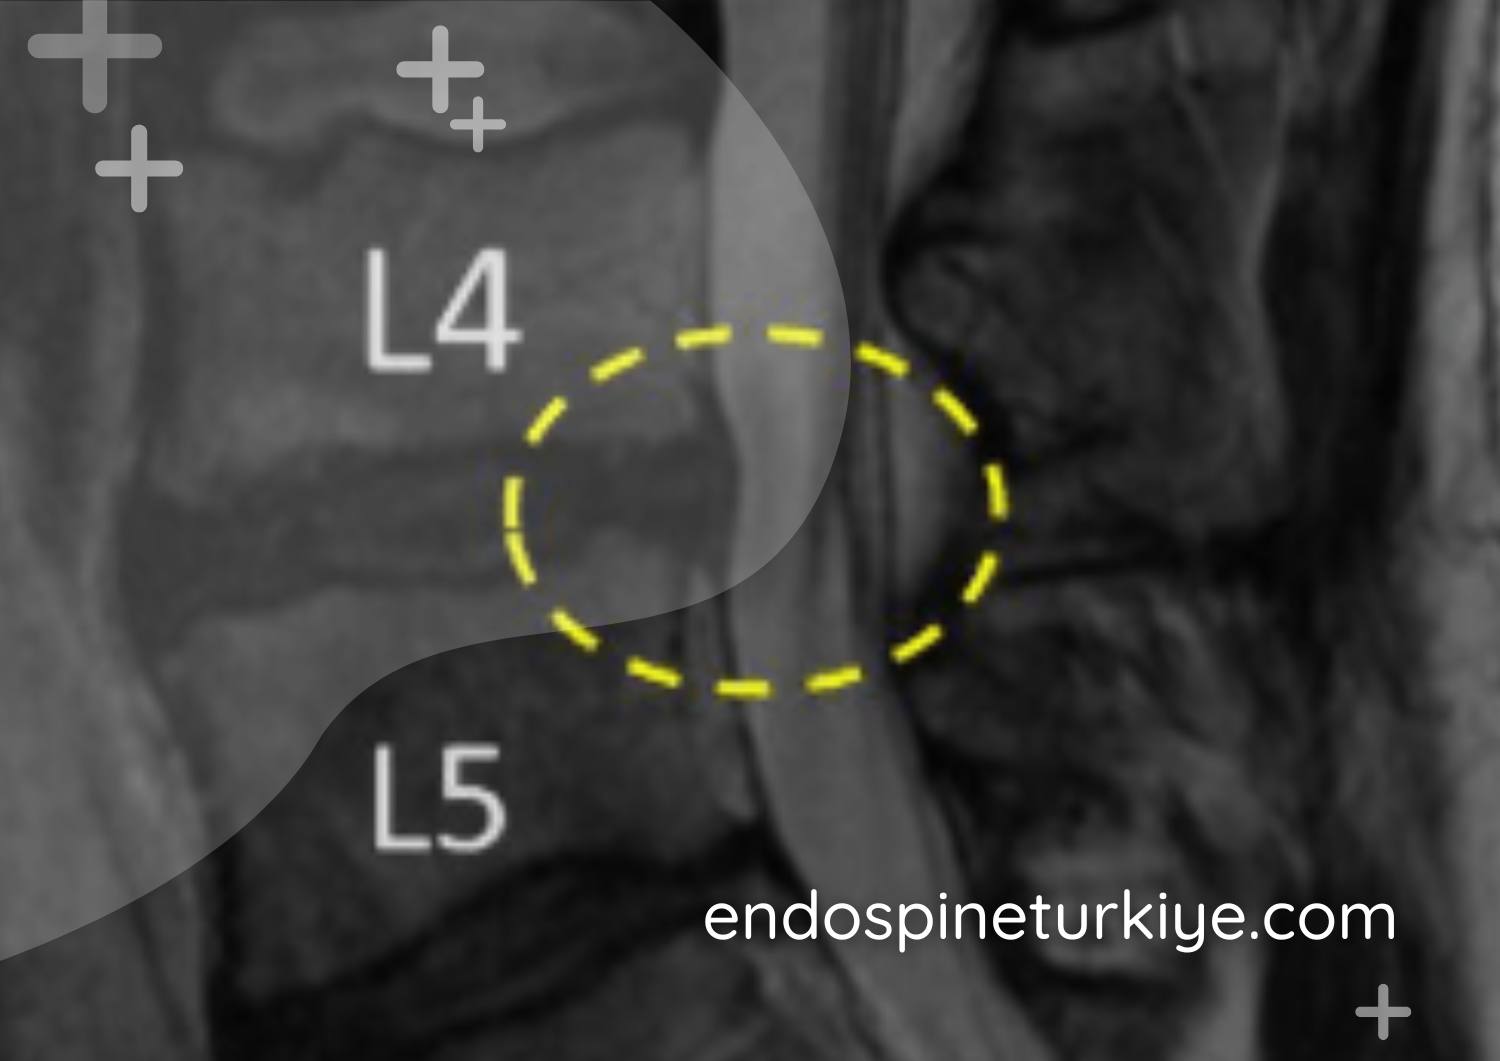

Omurga kanal daralması MR görüntüsü - Spinal stenoz teşhisi

Tedavi Öncesi

Daralmış spinal kanal